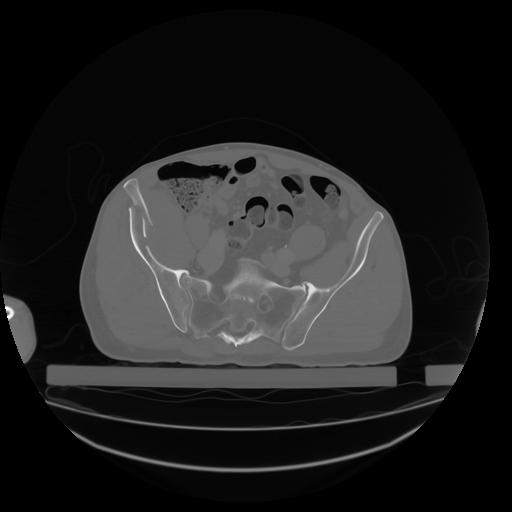

27 CUERPO,CE,Axial,3.0,CUERPO,,